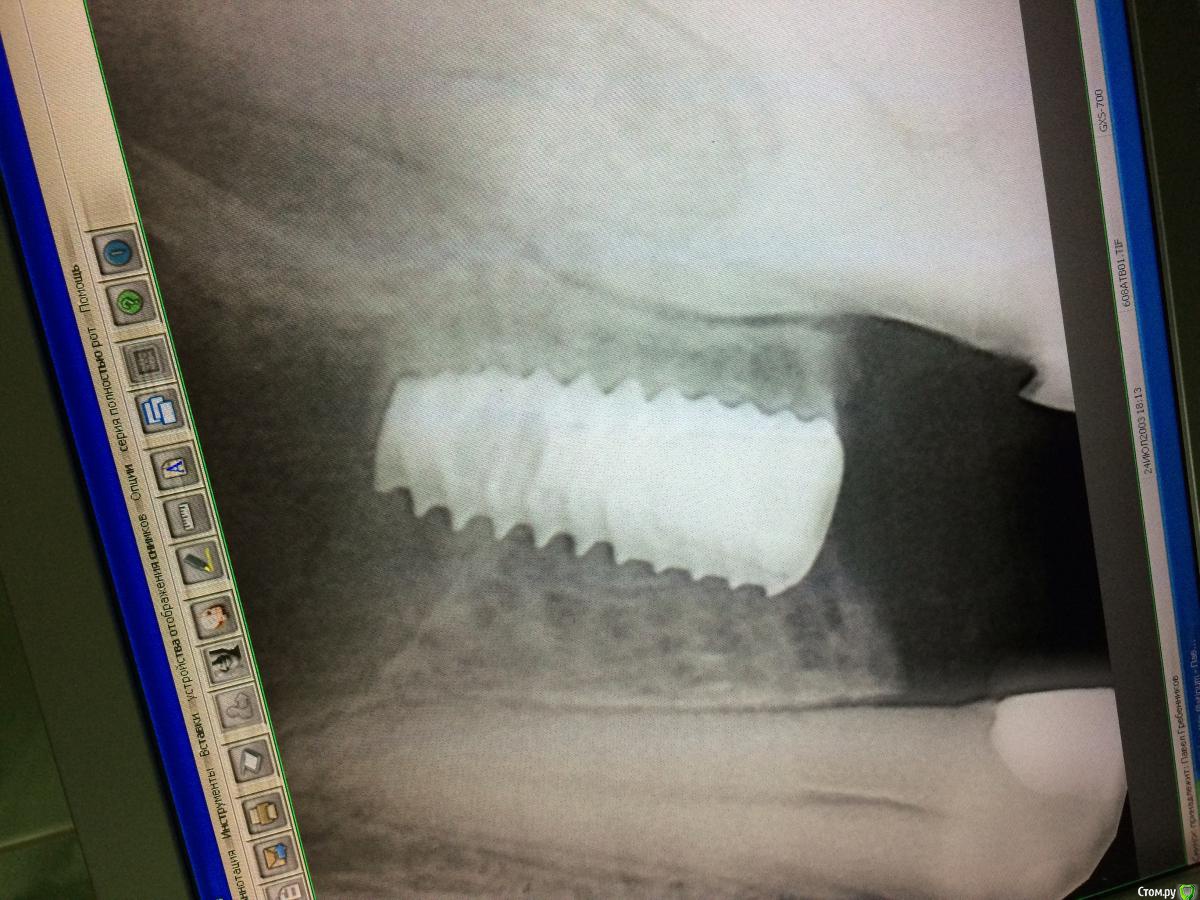

Graffwoman Опубликовано 25 февраля, 2018 Автор Поделиться Опубликовано 25 февраля, 2018 (изменено) внесу свою лепту Сосудосуживающий капли в нос на 10 дней - в каждый носовой ход Амоксиклав 1000 мг по 1 2 рд 5 дней либо супракс либо таваник - их легче принимать Бифиформ АциполНимесил 100 мг по 1 пакет 2 рд 7 дней Хлоргексидин или мирамистин - ротовые ванночки до 6 раз в день, потом сразу солкосерил дентальный наносить - он держится намного лучше других гелей и паст ,хватает трех раз в день Ну ,вообщем, это стандартный набор Из протокола хотел выяснить 1. чем сверлились ? был ли использован набор для закрытого синуса ?2. когда удаляли ( если это были Вы ) качественно ли был выполнен корежат?3.торк ?не вижу смысла трогать имплантат сейчас .Пусть заживает вторичным натяжением .Приживется - хорошо ,нет - переставите .Спасибо1.Стандартный набор Osstem2.Хороший вопрос.Прошло 1,5 года с момента удаления.Причину удаления сходу не вспомню ,но процесс был хроническим,без признаков воспаления.На верхушке корня после удаления была прикрепленная гранулема. .Кюретаж был ,как считали тогда- легкий (гранулема то вышла ),но качественный.Проба на соустье после удаления отрицательная.Сгусток формировался слабо,в лунку рыхло положила губку с йодоформом. Неожиданно лунка заживала плохо,вялотекущий альвеолит. Дополнительный неагрессивный кюретаж и промывание ХГ. .Но.... Через год- КТ и поняли,что кость не полноценная. На слизистой десны вроде легкое углубление-точка. Не придали значения,может,ревизию надо было сделать??? .Больше насторожил обьем слизистой в пазухе-до 25 мм,на сегодня -до 10). Долго ходил по ЛОРам -толку никакого. Решили оставить в надежде,может кость сформируется.,теперь снова вернулись.Всю остальную историю уже знаете. Прилагаю снимок первого КТ, по поводу размытой границы гайморовой -ничего пока не могу сказать,кажется,это просто такой ракурс. .3.Торк 45Сейчас принимает ципрофлоксацин третьи сутки по 500 мг 2р/д,антигистаминные, нимесил получается 2р/д,(тк к вечеру стал ныть снова),противогрибковые и для флоры кишечника. Как думаете ,а боль в проекции верхушки имлантата -откуда ? Изменено 25 февраля, 2018 пользователем Graffwoman Ссылка на комментарий

rytovst Опубликовано 26 февраля, 2018 Поделиться Опубликовано 26 февраля, 2018 боли одного характера ,одинаковой силы ?возможно была перфорация при удалении - трудно судить / много времени прошло вначале темы на прицельном снимке с медиальной стороны 2 витка резьбы в пазухе- может быть искажение.тут разговаривал с другим имплантологом - ставит смело при перфорациях Шнайдеровой - я не рискую.Откуда боль ? Вопрос хороший . как с перкуссией соседних зубов ? Ссылка на комментарий